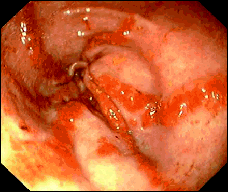

Endoscópicamente se reconocen dos formas: 1) longitudinal, que forma columnas eritematosas orientadas sobre los pliegues del antro (Figuras 1) y 2) difusa con múltiples lesiones rojizas puntiformes distribuidas de manera no uniforme en el antro (Figura 2). La forma difusa predomina en los pacientes cirróticos mientras que la longitudinal es más frecuente en los no cirróticos. El diagnóstico endoscópico de GAVE puede ser sumamente difícil por lo que se aconsejan las biopsias. La histología típica muestra ectasia capilar con trombos de fibrina e hiperplasia fibromuscular en la lámina propia.

Figura 1. Forma longitudinal de ectasia vascular antral gástrica formando columnas eritematosas orientadas sobre los pliegues del antro.